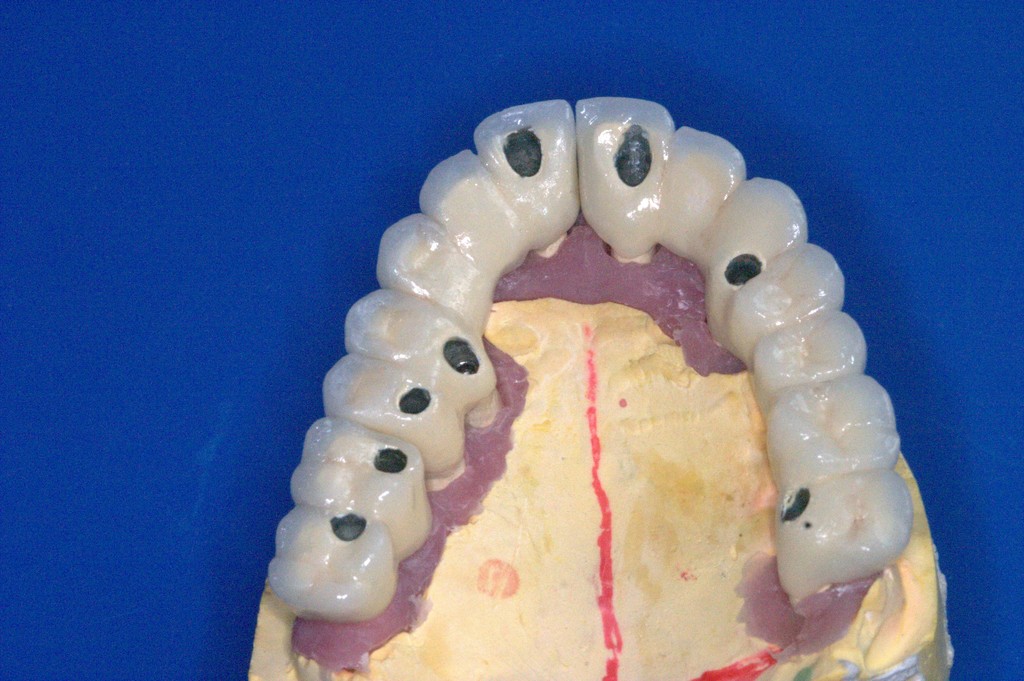

REHABILITACIÓN IMPLANTOSORTADA EN MANDÍBULA Y MAXILAR.

REHABILITACIÓN ESTÉTICA CON IMPLANTES.